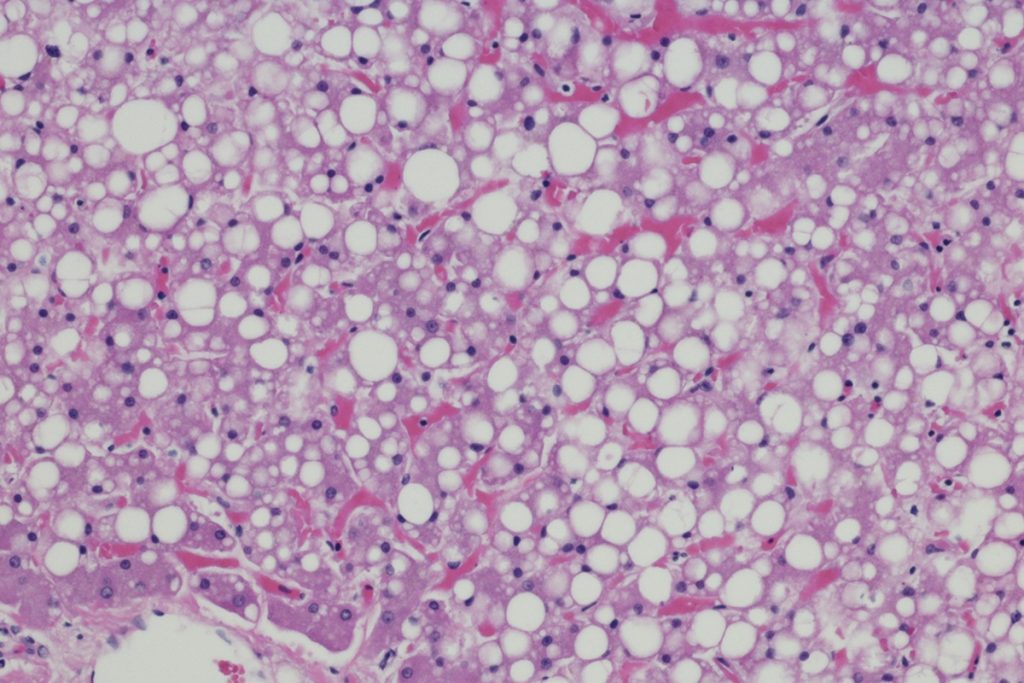

Cada vez mais comum entre os brasileiros, a esteatose hepática, conhecida popularmente como gordura no fígado, é uma condição muitas vezes silenciosa, mas que pode causar problemas sérios.

O quadro, que está relacionado à obesidade, sedentarismo e resistência à insulina, é caracterizado pelo acúmulo de células de gordura no tecido do fígado.

“O problema começa de forma discreta, mas pode evoluir para inflamações crônicas e fibrose, aumentando o risco de cirrose e câncer de fígado”, explica o endocrinologista Paulo Bittencourt, presidente do Instituto Brasileiro do Fígado (Ibrafig).